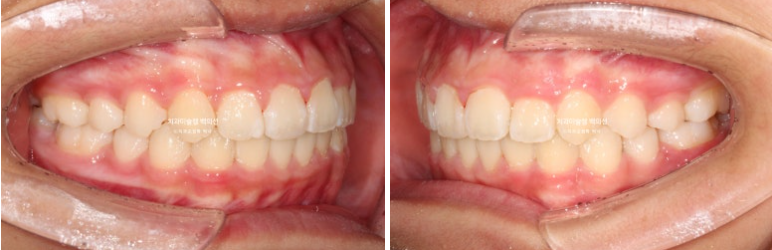

이제 전후비교 보겠습니다.

총 치료기간은 1년 6개월이며 중간에 중심선 이슈로 잠시 쉬는 시간이 4개월 있었습니다.

재제작은 총 2회 했습니다.

24.02~25.07

어긋난 중심선이 맞아졌으며 기울어진 앞니 치축도 좋아졌습니다.

앞니가 깊게 물리는 과개교합도 좋아졌습니다.